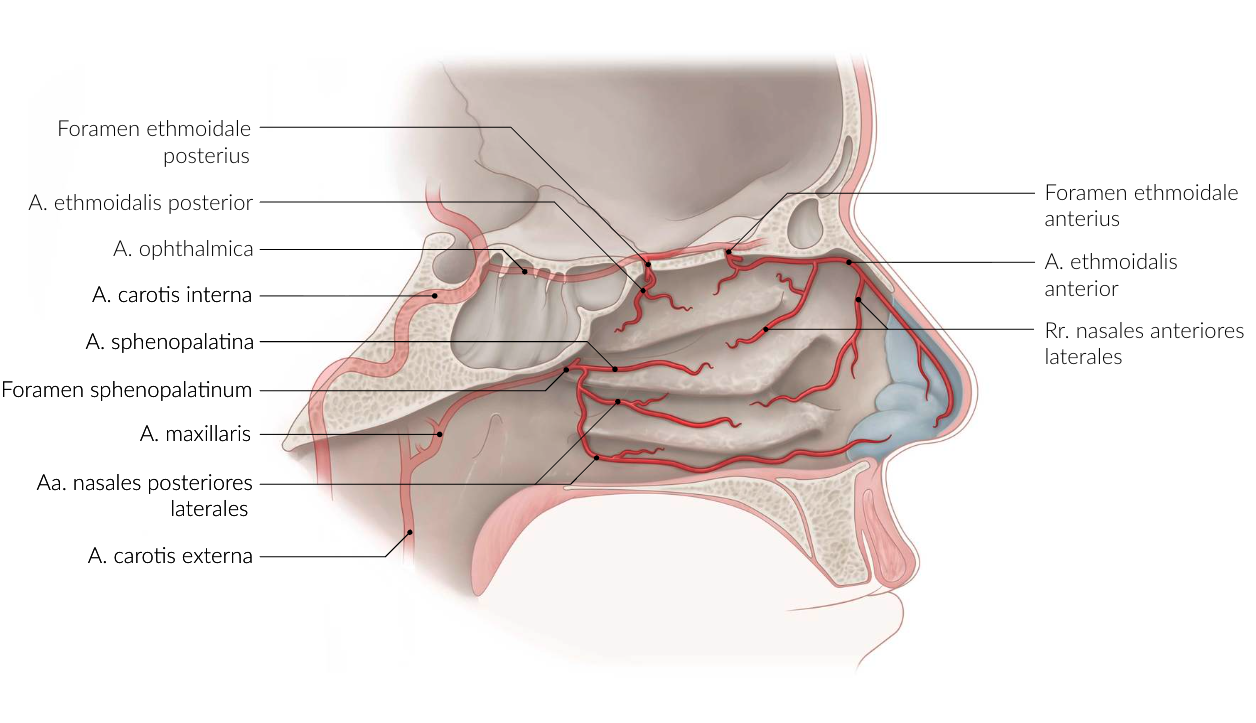

74. Nosebleeds (epistaxis) can occasionally be difficult to control and become life-threatening if arterial in origin. Such severe bleeding can originate from the posterior part of the nasal cavity. If other treatments fail, the affected artery can be therapeutically ligated.

Which artery is most likely involved in such cases?

A. Posterior superior alveolar artery (A. alveolaris superior posterior)

B. Anterior ethmoidal artery (A. ethmoidalis anterior)

C. Nasopalatine artery (A. nasopalatina)

D. Greater palatine artery (A. palatina major)

E. Sphenopalatine artery (A. sphenopalatina)